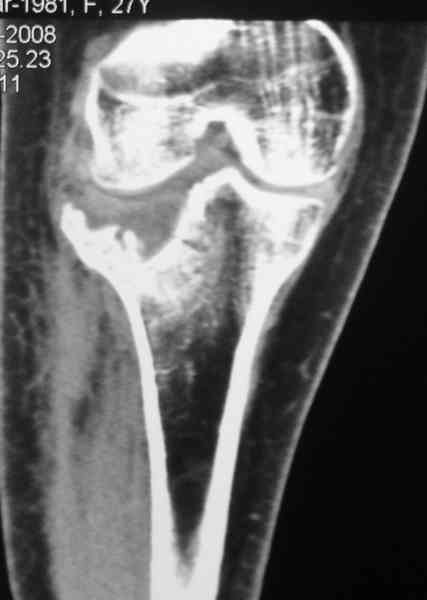

Re: Застарелый перелом 41С3

Уважаемый Ростислав. Спасибо что поправили, это у нас по старой привычке, "застарелый" наверное правильно будеть "неправильно вялоконсолидируюшаяся перелом" или есть еще другие варианты, надо подумать.

По тактике лечения, более импонирует второй вариант, но наружная плато расколота и туда при нагрузке внедряется н/мышелка бедра, поэтому после дистракции как репонирвать: или стяжными винтами, или изогнутами спицами или субхондральная костная пластика?

Уважаемый Абдурашид. Если нет противопоказаний , то из оперативных способов, я бы рекомендовал следующие: Полное замещение наружного мыщелка аллотрансплантатом либо открытая репозиция с элевацией и замещение дефекта ауто или аллокостью. В Ваших условиях , я бы рекомендовал второй способ. Во-время элевации необходимо разъединить фрагменты со стороны сустава ( надсечь скальпелем по линиям перелома, а затем тонким остеотомом их разъединить. При помощи долота произвести неполную остеотомию ( захватите не менее 1,5 - 2 см губчатой кости и поднять фрагменты, визуально отрепонировать и фиксировать 2-3 спицами. Дефект заместить костным ауто или аллатрансплантатом. Окончательная стабилизация пластиной ( лучше с угловой стабильностью, либо АВФ - позволит спокойно устранить угловую деформацию.